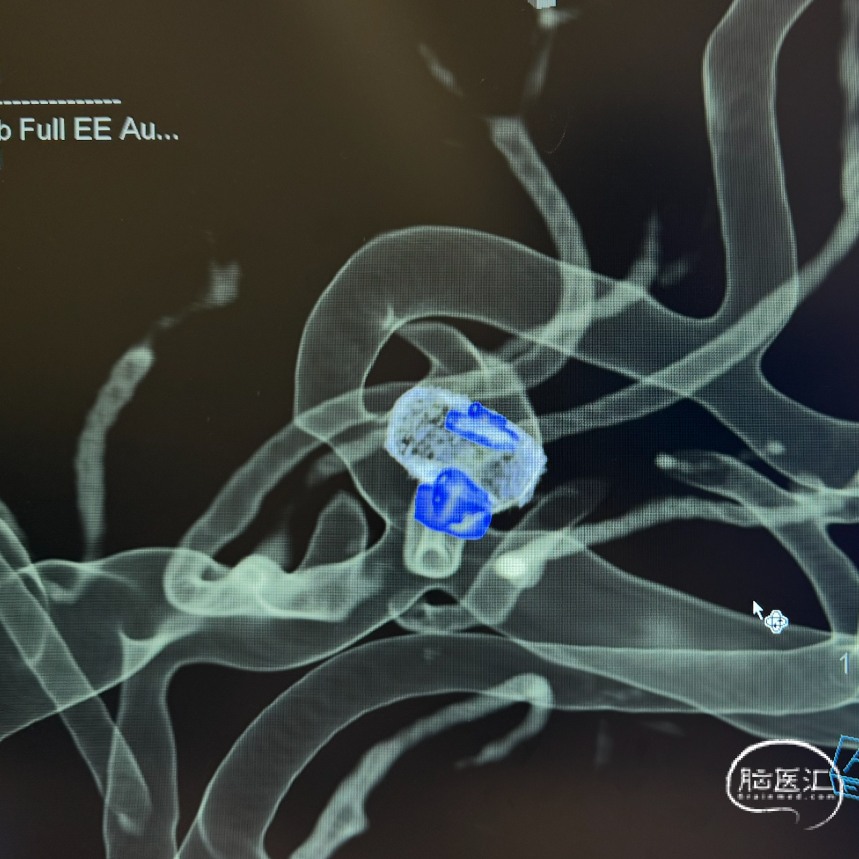

解脱后工作角度即刻造影,早额支及主干未受影响,动脉瘤内已可见血流分层。

术后三维重建及WEB™融合后图像,可见WEB™贴壁良好。

WEB™释放的实时评估:在成角部位,装置展开易受血流冲击影响。需通过多角度造影动态观察WEB™形态,重点确认瘤颈覆盖是否完全、尾端是否充分展开。本例通过反复调整,最终实现装置稳定贴壁,术后利用西门子自带多容积三维重建,分析扰流装置的位置,证实了技术操作的可靠性。